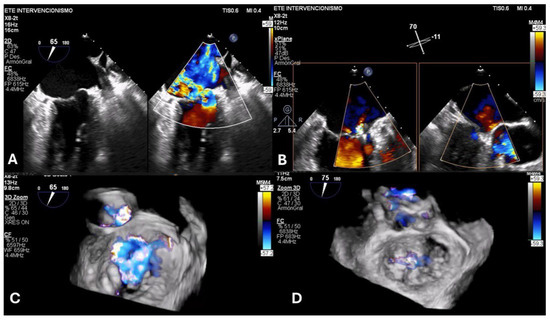

Background and Clinical Significance: Left atrial dissection is a rare surgical complication (occurring in 0.16% of cases), which results in the formation of a large cavity between the endocardium and the epicardium. Case Presentation: We report a case of a 78-year-old man [...] Read more.

Background and Clinical Significance: Left atrial dissection is a rare surgical complication (occurring in 0.16% of cases), which results in the formation of a large cavity between the endocardium and the epicardium. Case Presentation: We report a case of a 78-year-old man who underwent combined aortic and mitral valve replacement. Extensive debridement of the calcified mitral annulus most probably precipitated the formation of a dissection flap detected by transesophageal echocardiography after protamine administration. Profound hypotension and hemodynamic instability were treated with inotropic and vasopressor support and fluid administration without any further surgical intervention. Conclusions: The patient recovered uneventfully under conservative management, highlighting the importance of perioperative echocardiography for prompt diagnosis and tailored intervention. Full article

Show Figures

Figure 1